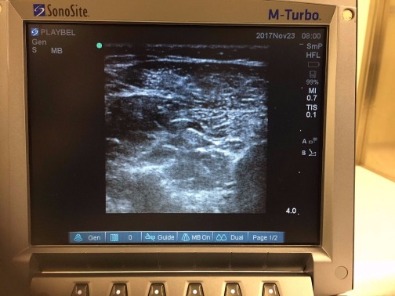

SONOGRAPHICALLY CONTROLLED BOTOX INJECTIONS

Botox (Dysport) injections are used to relax stiff muscles in patients with neurological problems, such as children with cerebral palsy and adults following a stroke. Botox (Dysport) is accurately injected in the muscle using an ultrasound scan. The injection is followed by casting and an intensive rehabilitation programme by professional physiotherapists specialised in neurological conditions. Even though it is possible to perform this procedure with the child awake, we prefer to perform Botox (Dysport) injections with an anaesthetic in theatre. This allows an examination which provides useful information for the future and accurate positioning of the injection. It is believed this method is kinder for the child.